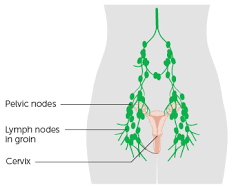

Lymph Node Biopsy Cervical or Axillary or Inguinal Under Ga

India

Hospital Price

$1700Our Price

$1530Overview

Package includes:

Days in hospital : 3 to 4 Days (For patient and one attendant)

Days in hotel : 5 Days (For patient and one attendant)

Room type in hospital : Shared

Room type in hotel : Private

Hotel category: Standard

Value added benefits of the Lymph Node Biopsy Cervical or Axillary or Inguinal Under GA: